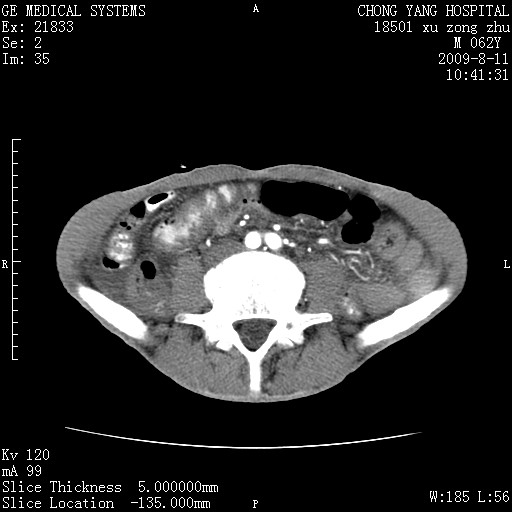

以下是引用杀毒软件在2009-8-11 16:35:00的发言:[br]肝内胆管扩张局限于左叶,胆管内有结石伴肝外胆管结石,胆管壁增厚呈弥漫性并发腹腔积液,胰腺边界模糊。[br][br]考虑---胆总管及肝内胆管结石继发胆管炎及胰腺炎,左肾下极囊肿,腹水。

以下是引用zjzjr在2009-8-11 17:35:00的发言:[br]肝内胆管扩张局限于左叶,胆管内有结石伴肝外胆管结石,胆管壁增厚呈弥漫性并发腹腔积液。[br][br]考虑---胆总管及肝内胆管结石继发胆管炎,左肾下极囊肿,腹水。